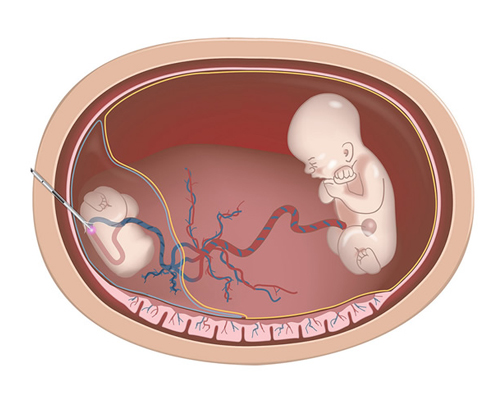

Understanding Fetal Reduction: What You Need to Know Before Making a Decision

What is Fetal Reduction? Fetal reduction, also known as embryo reduction or selective fetal reduction, involves decreasing the number of fetuses in the womb. Typically,